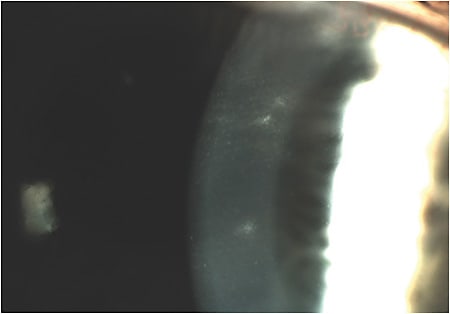

Corneal vascularization generally develops from a hypoxic post-lens environment or from chronic ocular surface inflammation. This oxygen-deficient environment leads to a release of pro-angiogenic cytokines from metabolically stressed cells that, in turn, leads to the development of blood vessels in the formerly avascular corneal tissue.11 Vascularization has been estimated to be present in 1% to 34% of the contact lens-wearing population, with a lower frequency in GP wearers; this is presumably due to greater tear exchange associated with GP lenses. The primary risk factors are wearing lenses overnight, high refractive errors, and low-oxygen-permeable (low-Dk) materials. Contact lenses that provide an oxygen transmissibility of 30 to 40 Fatt units or greater are thought to prevent the development of vascularization.11 Practitioners do need to consider that the central Dk/t of a lens is often misrepresentative of the Dk/t at the edge of the optic zone and the lenticular (if present). Therefore, with regard to high refractive errors, material selection is important.